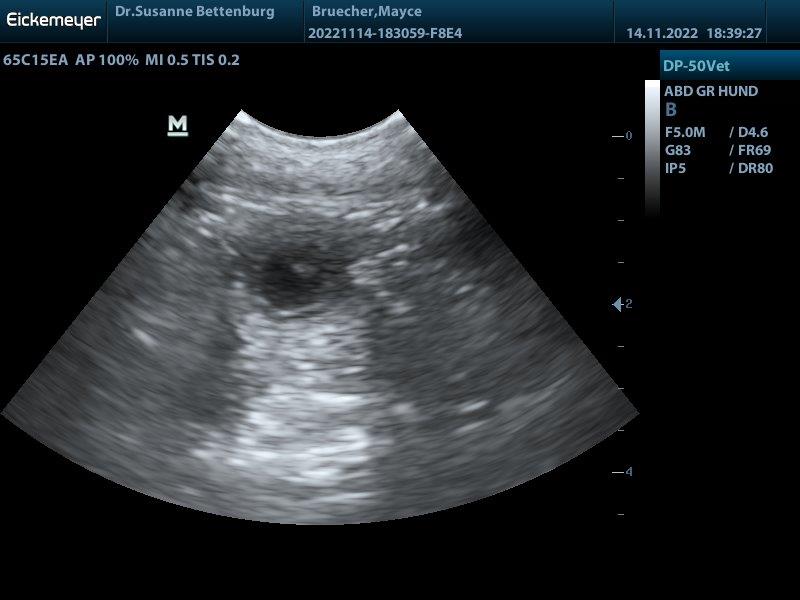

Juhuuu Mayce ist tragend wir haben viele Baby's gesehen

G-Wurf Mayce wurde am 23.10.2022 von Scotch gedeckt. In dem Wurf erwarte ich braune und schwarze Welpen